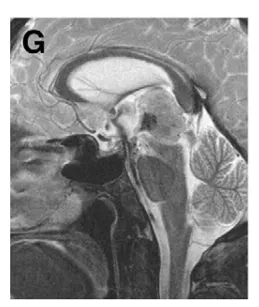

(G)术后第3天MRI,造瘘处可见显著流空信号;ETV后颅内压增高症状完全缓解。